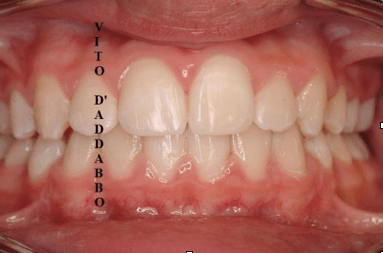

In una bocca che chiude correttamente i denti dell’arcata superiore sono collocati più esternamente rispetto ai corrispondenti dell’arcata inferiore. Nel morso inverso accade il contrario: in quello laterale sono i denti inferiori laterali a chiudere esternamente.

Questa malocclusione è il più delle volte dovuta a un mascellare piccolo, come nel caso riportato, dove manca anche lo spazio per l’incisivo laterale permanente di sinistra. I morsi incrociati vanno corretti precocemente perché possono provocare gravi asimmetrie del viso.

dopo